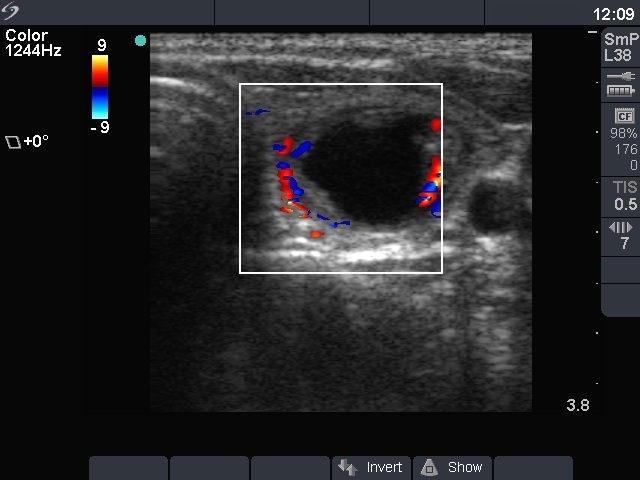

Ethanol sclerotherapy: thyroid cysts - Case 11

First session of the therapy (ultrasonographic picture 3)

Left lobe, horizontal scan, color Doppler mode. The lesion has a perinodular blood flow.